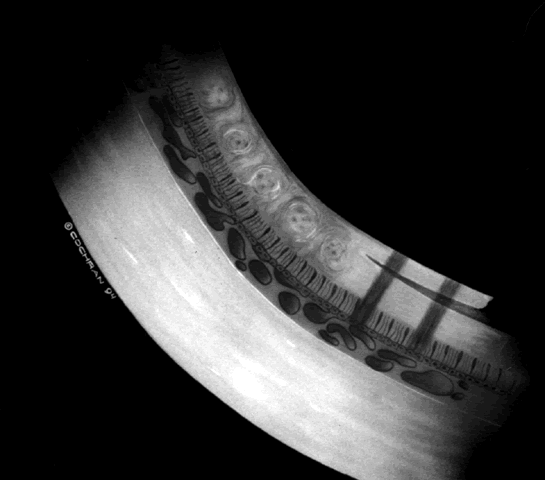

ROP accounts for a large number of retinal detachments in the pediatric population. The International Classification of Retinopathy of Prematurity helped greatly to improve communication about, and consequently treatment of, ROP. It describes affected eyes in terms of stage, zone, and absence or presence of plus disease18 (Figs. 1, 2, and 3). Screening of premature infants is an important feature in the care of ROP, which is perhaps the most significant and enduring finding of the Cryotherapy for Retinopathy of Prematurity Study (Cryo-ROP Study).19

Fig. 2. Standard zoning patterns of retinopathy of prematurity. Zone 1 is defined as a circle with a radius of two times the distance between the center of the optic nerve and the foveola. Zone 2 is a circle whose radius is from the center of the optic nerve to the nasal horizontal ora serrata. All the remaining area of retina is zone 3.